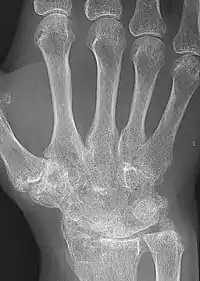

X-ray of the wrist of a woman with rheumatoid arthritis, showing unaffected carpal bones in the left image, and ankylosing fusion of the carpal bones eight years later in the right image

The disease progresses by forming granulation tissue at the edges of the synovial lining, pannus with extensive angiogenesis and enzymes causing tissue damage.[63] The fibroblast-like synoviocytes have a prominent role in these pathogenic processes.[17] The synovium thickens, cartilage and underlying bone disintegrate, and the joint deteriorates, with raised calprotectin levels serving as a biomarker of these events.[64] Importantly inflammatory events are not limited to synovium but it appear to be systemic, evidence suggest that alterations in T helper profile favoring inflammation such as inflammatory IL-17A producing T helper cells and pathogenic Th17 cells are come from both memory and effector compartment in RA patients peripheral blood.[65]